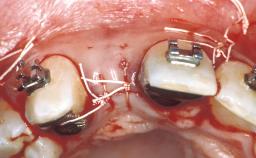

Replacement of Multiple Teeth in a Partially Dentate Posterior Mandible with a Fixed Dental Prosthesis Using a Flapless Approach

Her chief complaint was her inability to masticate efficiently due to the recent loss of her mandibular second premolars and first molars bilaterally. She expressed a desire for fixed prostheses in the shortest possible time due to her advanced age, requesting that replacement teeth should look as natural as possible. She was otherwise comfortable and not experiencing any symptoms from her teeth.

Guided Surgery Yes

Abutment Type Customized

Prosthesis Type FDP

Retention Screw-retained, with 2 splinted implants Screw-retained, with 2 splinted implants